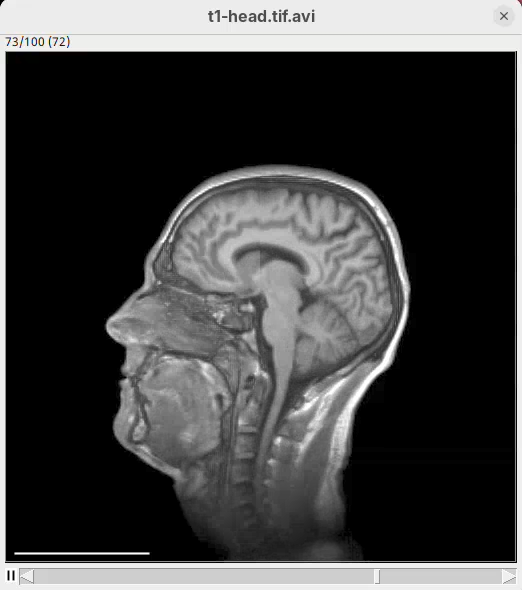

Animation 3D

Now that we learned the basics of setting up the rendering and view parameters, we can start generating animations of the data.

- Click on the

Animationsection and on theStart text-based animation editorbutton.

This will open a special editor window for writing the animation script.

Rotate horizontally

Let’s start with the simplest animation: a rotation of the head around 360 degrees. We need to define the number of frames that the animation will have and what will happen during these frames. We can start by defining that the animation will have ten frames.

Note: frame counting in 3Dscript begins from 0 (frame 0 to 9 has 10 frames).

The editor has a strong autocomplete; you only need to type one letter at a time to be able to write the exact text needed for the animation.

- Type

f. The editor will autocomplete withFrom frame <frame>. - Type

0and space. The autocomplete will fill withFrom frame 0 to frame <frame>. - Type

9and space. The autocomplete will show a dropdown menu with several options (rotate by,translate,zoom by a factor of,reset transformation, andchange). - Choose

rotate byand pressTab. The autocomplete will showFrom frame 0 to frame 9 rotate by <degrees>. - Type

360and space. The sentence will beFrom frame 0 to frame 9 rotate by 360 degreesand a dropdown will show the optionshorizontally,vertically, andaround. - Choose

horizontallyand on the next menu choose(none).

We have our first animation script and it’s just this single sentence:

From frame 0 to frame 9 rotate by 360 degrees horizontally- Press

Run.

A new window will show up with an image stack of 10 frames containing the generated animation.

- Press play or and watch the head turn 360 degrees during these 10 frames.

Note that we did not need to define how many degrees the head would turn for each frame. We can simply state that we need the head to turn 360 in these 10 frames and 3Dscript will deal with it.

Make it smoother

Our first animation is cool, but a bit jumpy. To make it smoother we can add more frames.

- Change the final frame from

9to35, so that the animation will have 36 frames in total.

Now each frame rotates by 1 degree and the animation is much smoother.

Add easing

The standard animation creates a linear rotation; every frame turns a fixed number of degrees. 3Dscript can add easing to create non-linear transitions by accelerating or decelerating the rotation.

- Type

easeat the end of the script sentence:

From frame 0 to frame 35 rotate by 360 degrees horizontally ease- Then, press

Run.

The left head is the one without easing (linear transition) and the right head is the animation with easing. Note how the right head accelerates the rotation at the beginning, turning much faster, and then decelerates towards the end of the rotation. Both end the rotation at the same time. Play both animations side-by-side to see the difference (it’s very clear, once you see it).

Animate cropping

Let’s add a couple more commands below our rotation sentence. We want that, after the 360 degree rotation, the animation slices through the head to show the tissues inside. For that, we can change the cropping parameters to control the position of the bounding box during the animation.

- After the first sentence, write the two commands as shown below:

From frame 0 to frame 35 rotate by 360 degrees horizontally

From frame 36 to frame 71 change channel 1 bounding box min z to 60

From frame 72 to frame 99 change channel 1 bounding box min z to 0- Press

Run.

The script is saying to rotate 360 degrees horizontally, as before, set the Z range minimum to 60 (roughly halfway through the sample) for about 30 frames, and then set the Z range minimum back to 0 in the subsequent 30 frames. And that’s what we get.

Define multiple commands

Another useful 3Dscript feature is the ability to issue multiple commands to happen simultaneously, within the defined frames. For example, we can make a script that defines a horizontal rotation and Z cropping at the same time.

- Write the code below in the editor and press

Run:

From frame 0 to frame 71:

- rotate by 270 degrees horizontally

- change channel 1 bounding box max z to 60Now cropping is happening simultaneously with the rotation.

- zoom by a factor of 2Tweak appearance

We can now also tweak the animation to reach the final appearance that we want. For example, we can change scale bar width and height and hide the bounding box lines around the sample.

- Write the code below in the editor and press

Run:

At frame 0:

- rotate by 90 degrees around (0, 1, 0)

- change channel 1 bounding box z to (0, 129)

- change bounding box visibility to off

- change scalebar length to 50

- change scalebar width to 10

- change scalebar offset to 20

From frame 0 to frame 71:

- rotate by 180 degrees horizontally

- change channel 1 bounding box max z to 60

- zoom by a factor of 2

From frame 72 to frame 100:

- change channel 1 bounding box max z to 129

- zoom by a factor of 0.5Note how there’s no longer a bounding box and the scale bar is much more visible.

This ends this part of the tutorial using a single-channel, single-timepoint dataset. Save the animation script to file for later re-use or incremental improvements.